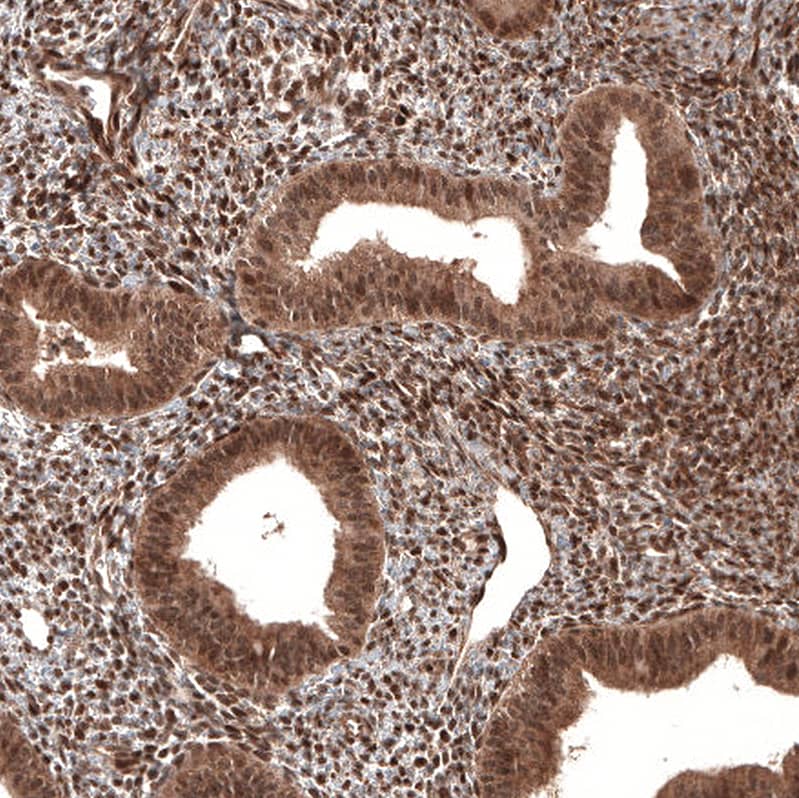

Staining of human endometrium shows strong nuclear positivity in cells in endometrial stroma.